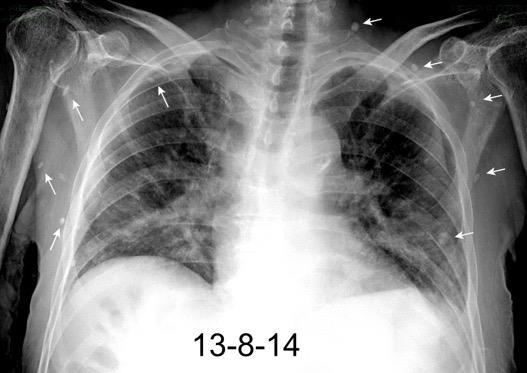

Radiografía AP en politraumatizado con enfisema subcutáneo severo.

Kumar H M,et al. Ginkgo leaf sign and subcutaneous emphysema.BMJCase Rep .2018